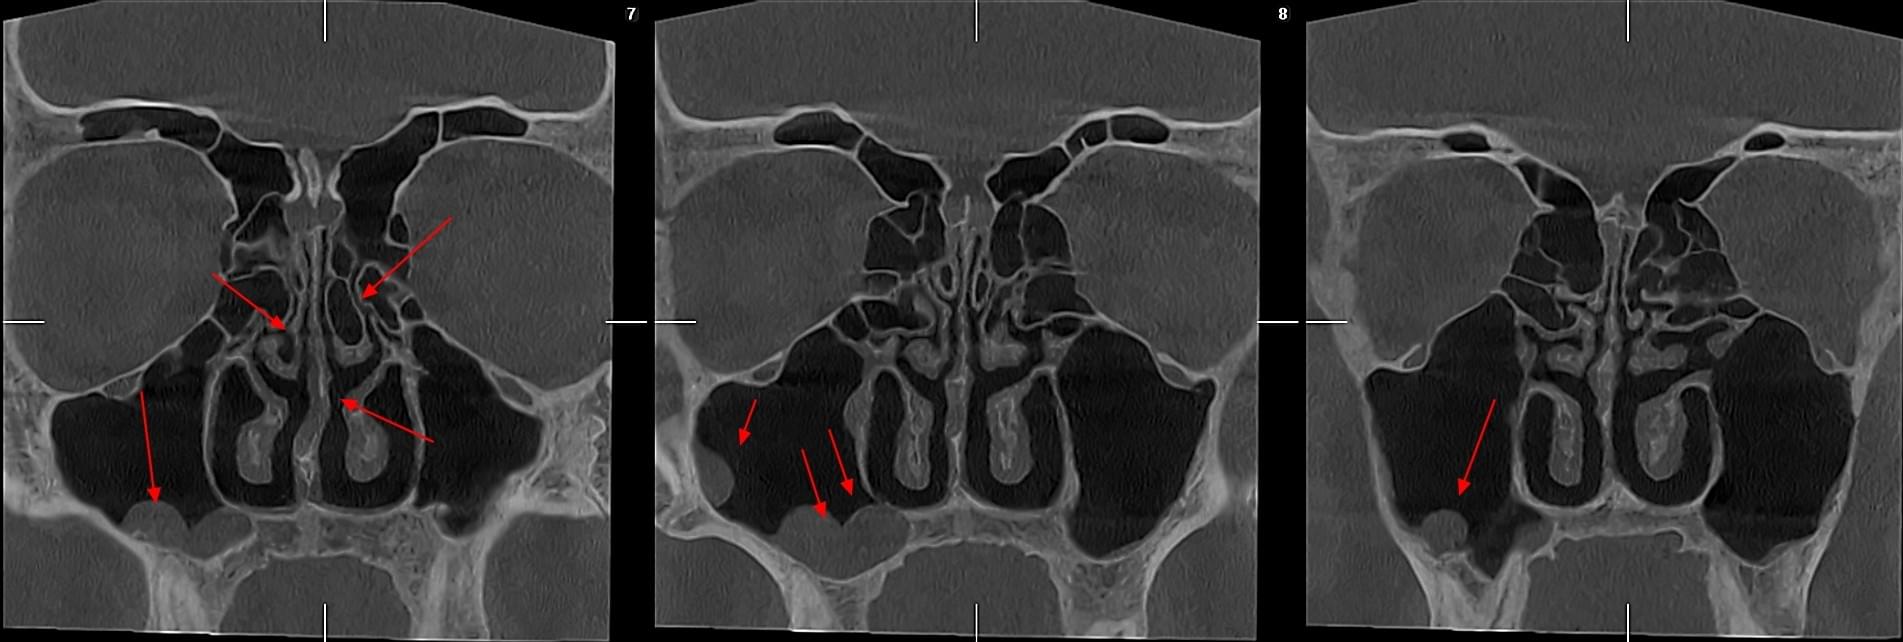

КПКТ (конусно-променева комп’ютерна томографія) — це 3D-знімок високої роздільної здатності. На відміну від звичайного рентгену, КТ показує:

ЛОР призначає обстеження у таких випадках:

КТ дозволяє провести віртуальну операцію: встановити імплант у програмі, виключивши будь-які ризики травмування пацієнта.